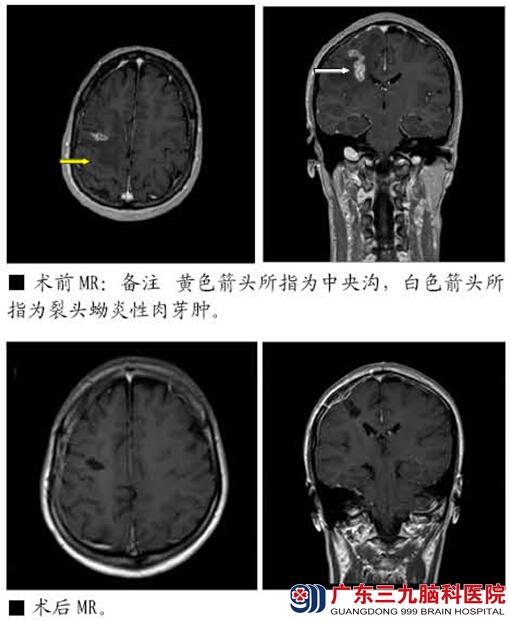

患者林某,女,32岁,主诉“发作性意识不清伴左侧肢体抽搐2年余,核磁共振示右额中央区病变”于2013-07-18入院。

患者于2011年3月份无明显诱因出现意识不清,头部向左侧偏转,双眼向上凝视,四肢僵硬伴抖动。持续数分钟后自行缓解,4小时后患者再次出现一次上述症状。至当地医院行头部核磁共振示右额中央区占位病变,考虑炎性肉芽肿可能,予卡马西平 0.2g tid治疗。患者仍有癫痫发作,表现形式:2011-2012上半年主要表现为面肌抽搐;2012下半年为左侧肢体抽搐;持续时间约1分钟,有时仅出现肢体、面部麻木感,发作过程中患者意识清楚。每年发作约10次。既往食用过未煮熟青蛙史。查体:生命体征平稳,神清,颅神经检查未见明显异常。脑膜刺激征阴性,四肢肌力正常,肌张力无明显改变。感觉系统检查未见异常。生理反射存在,病理征未引出。入院后头颅MR提示右额中央区异常强化灶,病灶形态与位置较前变化,范围较前略大,周围水肿大致同前,考虑裂头蚴脑病可能性大。诊断:1.症状性癫痫(复杂部分性发作,部分性发作继发全面性发作)2.右额中央区病变(脑裂头蚴病可能性大)。于2013-07-25在术中唤醒及导航下行右侧额中央区病变切除术,手术顺利,术中取出活虫一条,长约6cm。术后患者无再出现癫痫发作,四肢肌力同术前,肌张力无明显改变。感觉系统检查未见异常。